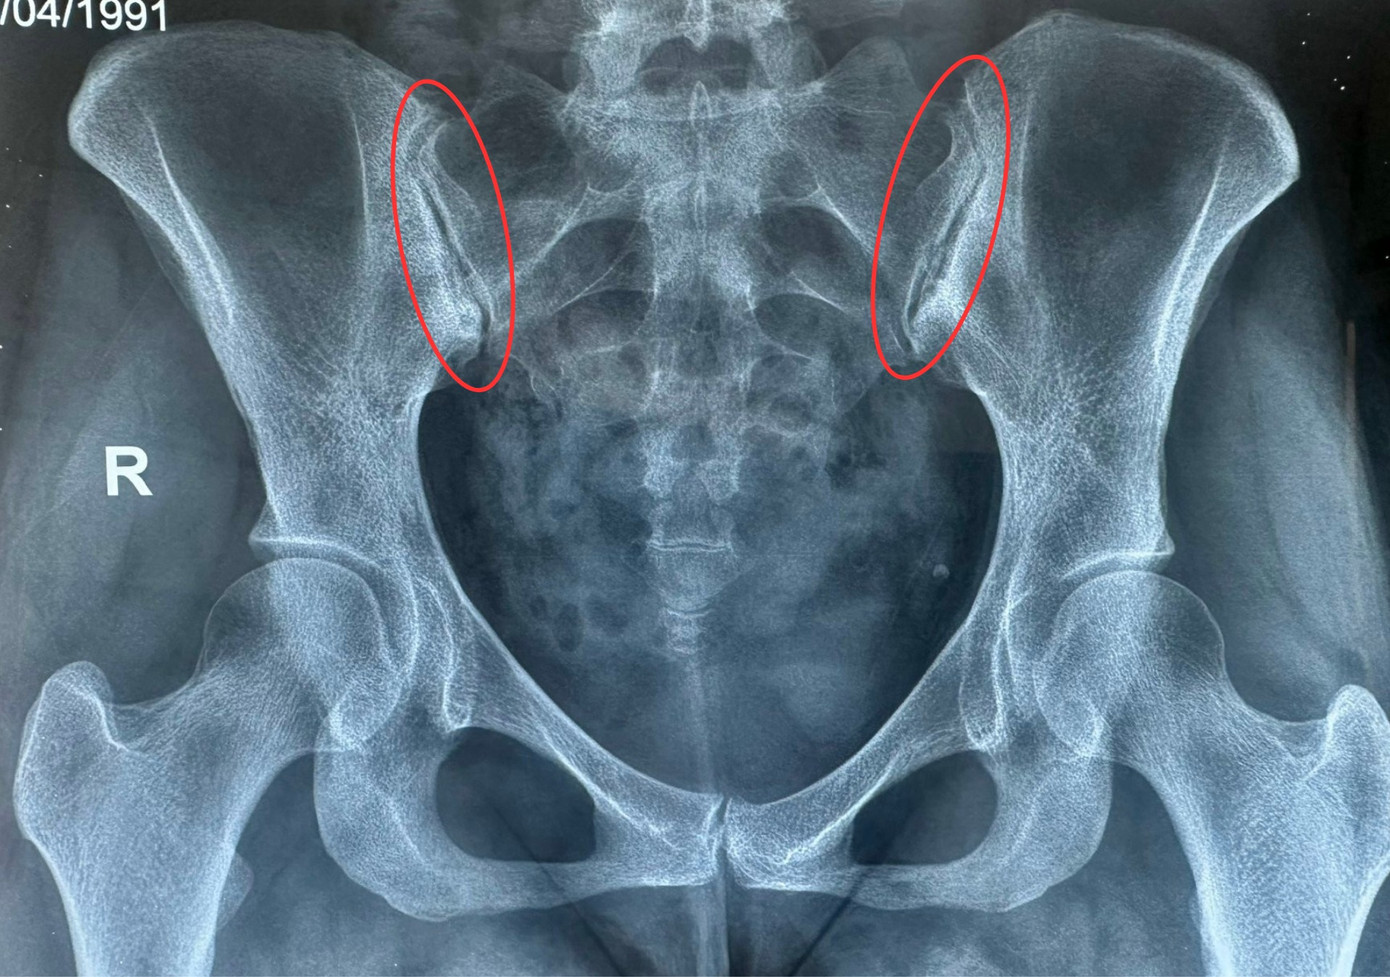

Đến khám tại Chuyên khoa Cơ Xương Khớp - Bệnh viện Đa khoa Hồng Ngọc, qua các xét nghiệm và thăm khám lâm sàng, bác sĩ CKI Dương Thị Thủy phát hiện bệnh nhân mắc Viêm cột sống dính khớp thể hỗn hợp HLA B27 (+), đây là nguyên nhân của tình trạng đau lưng và đau hệ thống các khớp (khớp cùng chậu, gối, ngón tay, bàn chân,...).

Chia sẻ về tình trạng của chị H, bác sĩ Thủy cho biết thêm: “Thách thức trong ca bệnh này là bệnh nhân mắc Viêm cột sống dính khớp thể hỗn hợp HLA B27 (+), một thể bệnh viêm cột sống dính khớp khá phức tạp, triệu chứng liên quan đến nhiều khớp và nhiều vị trí khác nhau. Nếu như không điều trị tập trung và hiệu quả, không chỉ cột sống mà hệ thống các khớp khác khắp cơ thể người bệnh như: khớp cùng chậu, khớp gối, khớp ngón tay và bàn chân,... đều bị ảnh hưởng, nguy cơ tàn phế cao.”